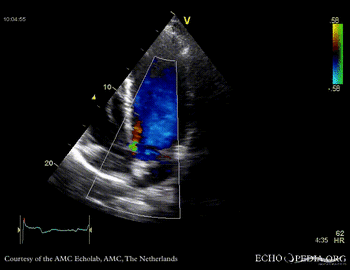

Case 10